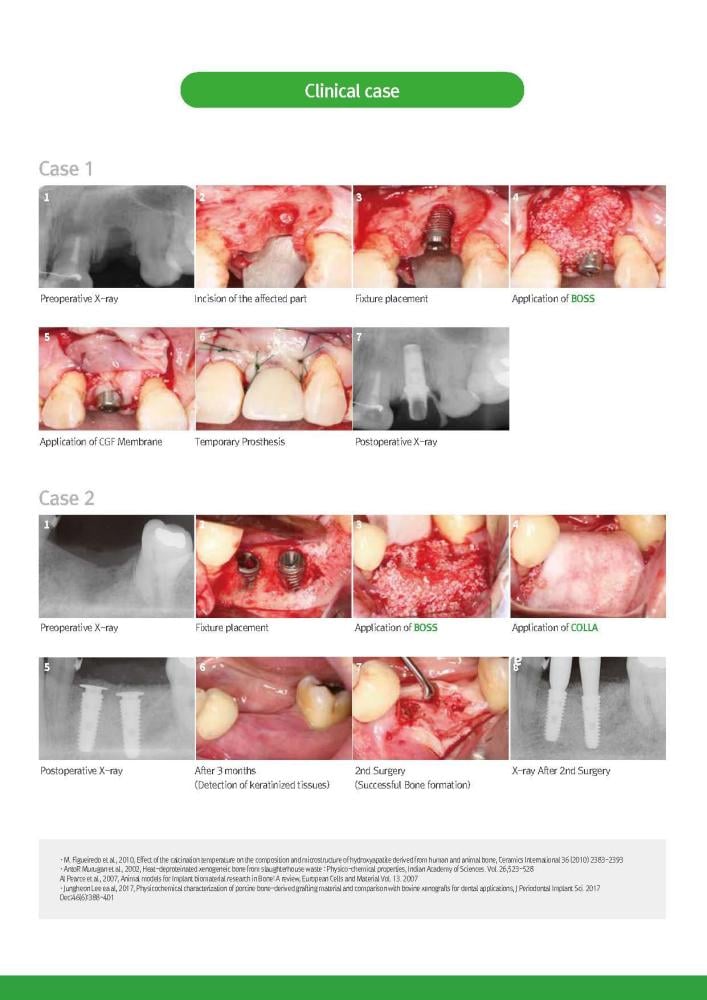

Medpark BOSS Bovine Bonegraft 1.0 CC

Medpark Colla Membran 30X40mm

Medpark BOSS Bovine Bonegraft0.5 CC

Medpark Colla Membran 10X20mm

Medpark Colla Membran 20X30mm

Medpark Colla Membran 15X20mm